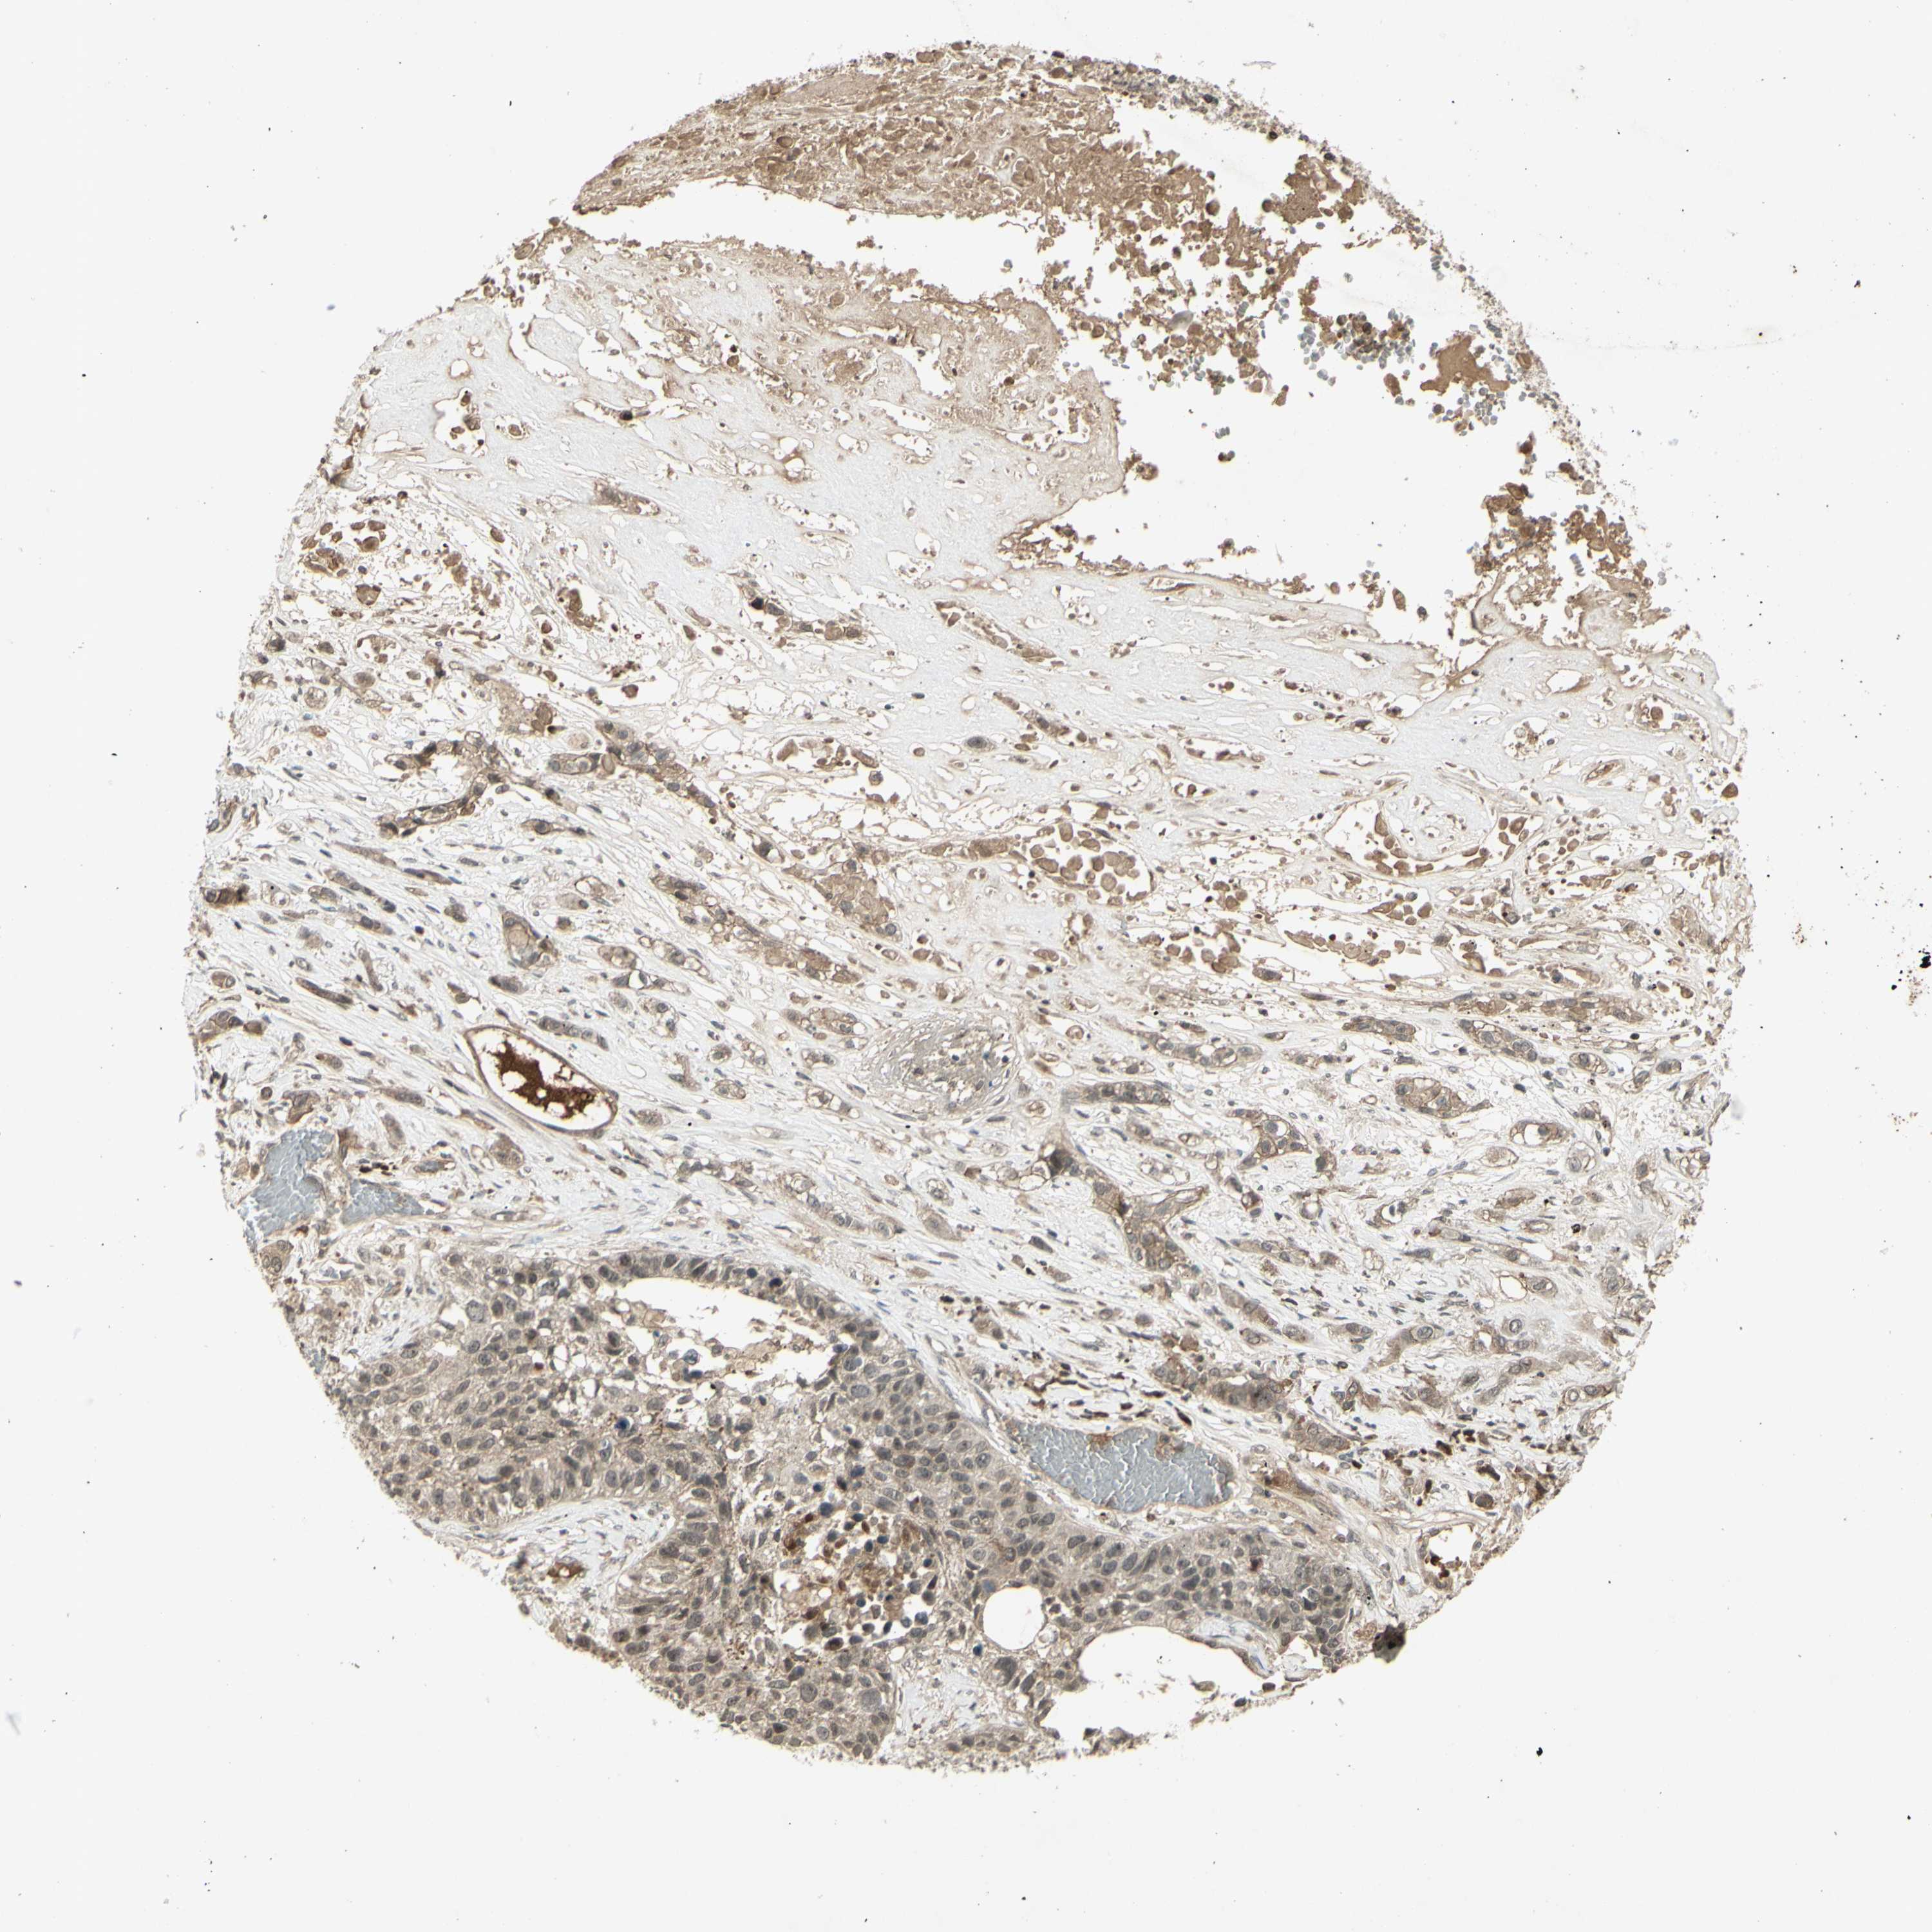

CANCER LUNG CANCER Show tissue menu

LUAD TCGA LUAD VALIDATION LUSC TCGA LUSC VALIDATION PROTEIN LUAD CPTAC PROTEIN LUSC CPTAC PROTEIN EXPRESSION

ANTIBODIES

AND

VALIDATION